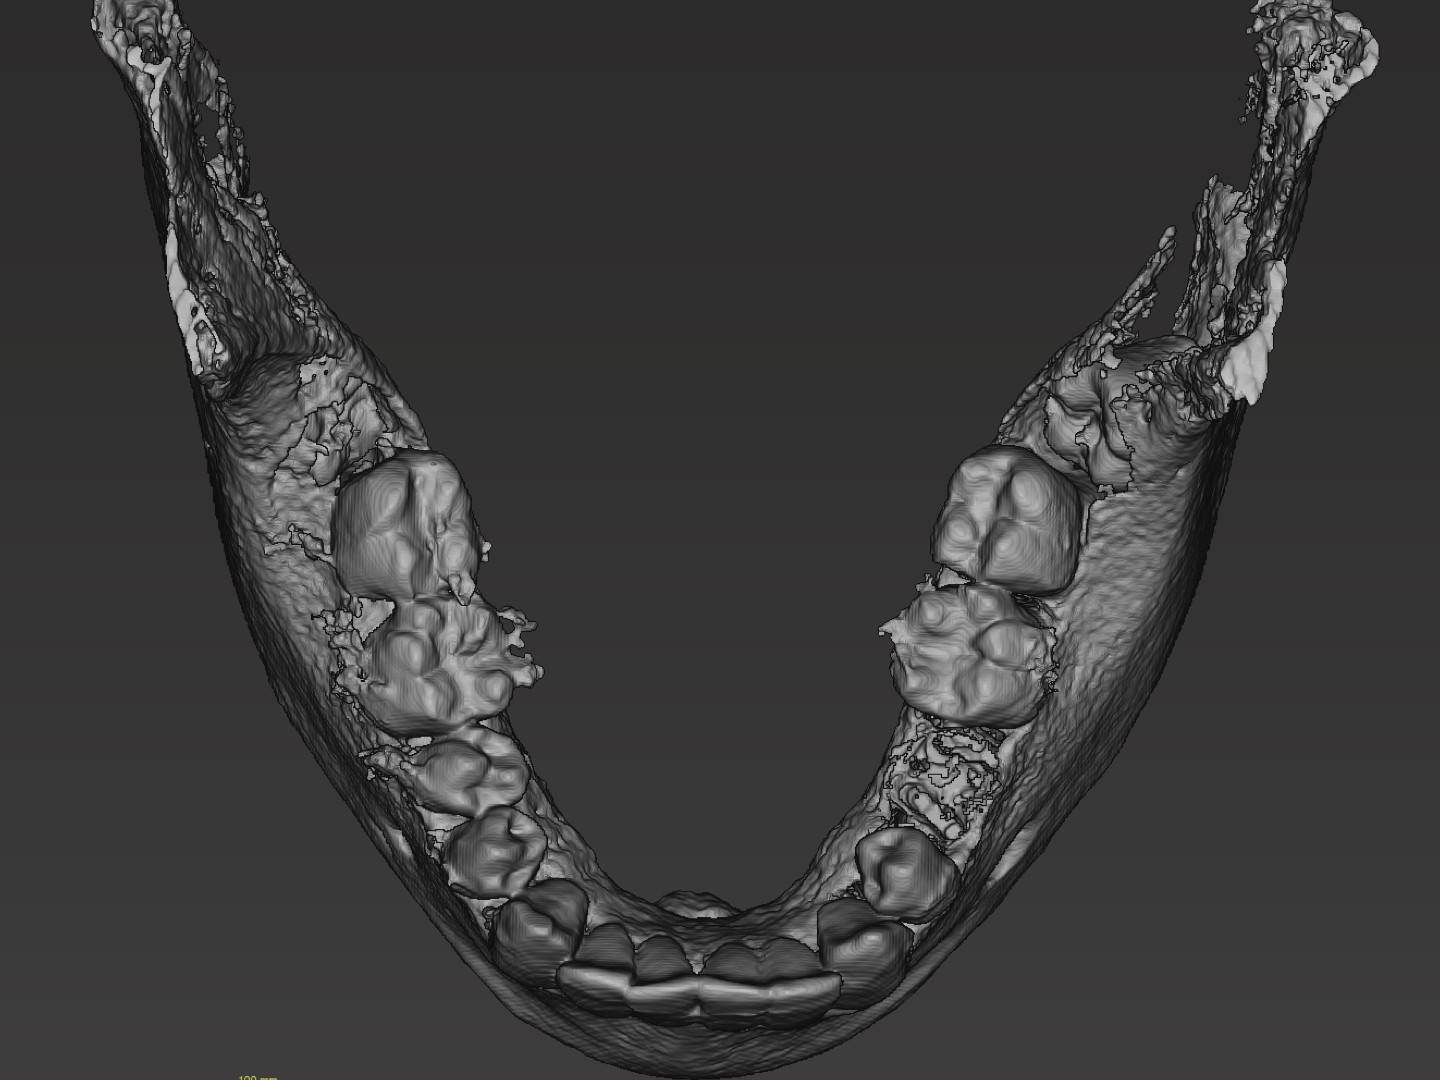

Der Zahntechniker importierte den Datensatz und segmentierte diesen im Anschluss entsprechend der Vorgaben des Chirurgen. Unter Segmentierung versteht man das „Reinzeichnen“ der knöchernen Strukturen, sprich, das Entfernen von Strahlungsartefakten. Im Unterkiefer erfolgte die Segmentierung als Ganzes. Darüber hinaus wurden die Zähne 18, 28, 38 und 48 einzeln dargestellt. Für eine fehlerfreie Darstellung des Knochens und der Zahnhartsubstanz müssen die Schwellwerte vom Zahntechniker in der Software exakt definiert werden. Im Anschluss an den so erstellten Datensatz erfolgte das Exportieren des Unterkiefers sowie der einzelnen Zähne als STL-Datensatz.

Damit die so erstellten Datensätze der Zähne im Nachgang auch im Handling einwandfrei sind, fügte der Zahntechniker mithilfe des externen CAD-Programms Meshmixer (Autodesk) aus okklusaler Richtung jeweils einen STL-Datensatz einer Stecknadel an. Somit konnte der Chirurg die Zähne problemlos greifen und austesten, welcher Zahn für die Lücke infrage kam. Die so gewonnenen Datensätze wurden auf ihre Konsistenz geprüft, bereinigt und für den 3-D-Druckprozess validiert. Abschließend erfolgte die Umsetzung im 3-D-Druckverfahren und der Versand in die chirurgische Praxis (Abb. 4–9).